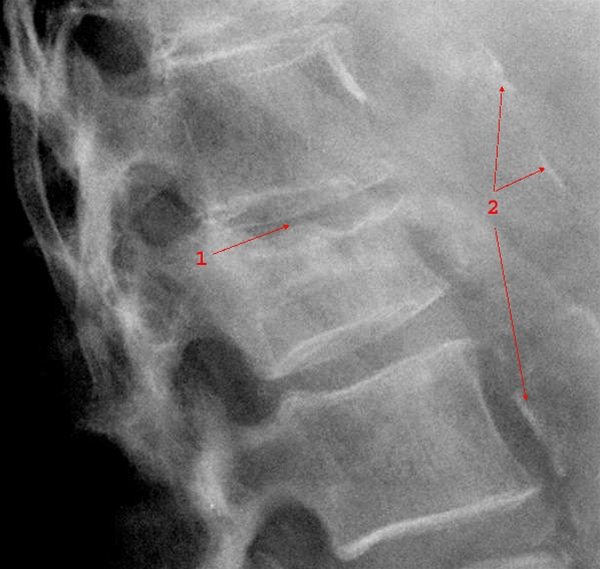

Columnafraktur sidebillede

1. Kompressionsfraktur, sammentrykket ryghvirvel

2. Karvægsforkalkninger i aorta (bifund)